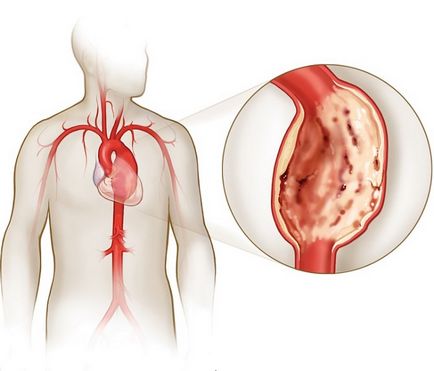

- в результаті порушення ліпідного обміну, збоїв в роботі процесів згортання крові або з інших причин відбувається утворення згустків крові. Вони «закріплюються» на місцях пошкодження внутрішніх стінок судин;

- поступово згусток розростається і переростає в тромб, який перекриває прохід крові;

- через нестачу харчування клітини починають відмирати. В результаті орган перестає виконувати свої функції.